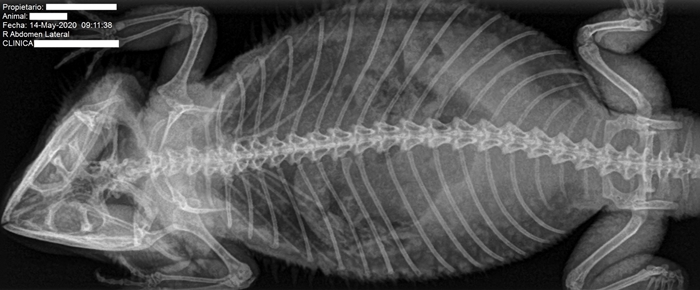

Tras la exploración por parte de su veterinario se decide realizar estudio radiográfico abdominal al paciente.

DXIA revisa y analiza junto al veterinario dicho estudio radiográfico observando en las radiografías, en zona de proyección de los folículos ováricos, estructuras de densidad de tejido blando levemente heterogénea y se decide realizar estudio ecográfico.